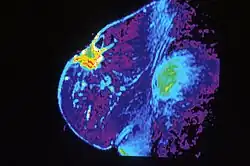

Mammography is the process of using low-energy X-rays (usually around 30 kVp) to examine the human breast, which is used as a diagnostic and screening tool. The goal of mammography is the early detection of breast cancer, typically through detection of characteristic masses and/or microcalcifications.

In addition to diagnostic purposes, mammography has interventional utility in stereotactic biopsies to precisely locate and find the area of concern and guide the biopsy needle to this precise location. This ensures that the area biopsies correlates to the abnormality seen on mammogram. It is called stereotactic since it uses images taken from two different angles of the same location. A biopsy is indicated when small accumulations of calcium are seen on mammogram, but cannot be felt on physical exam and do not appear on ultrasound.